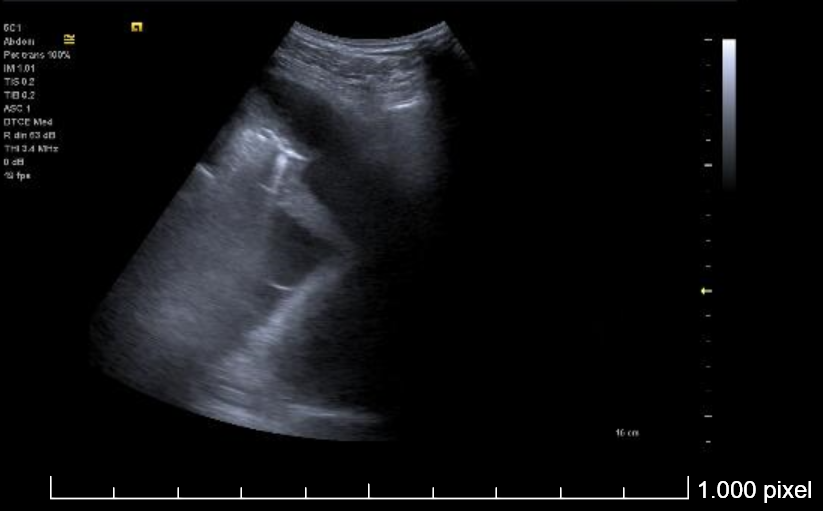

Ecografía torácica:

Derrame pleural izquierdo de 4 espacios intercostales, libre, hipoecogénico, sin ecos internos. Lóbulo pulmonar inferior izquierdo con imagen de patrón mixto (Intersticial y consolidación).

Se realiza toracocentesis diagnóstica y evacuadora con la paciente en decúbito lateral derecho. Se drenan un total de 550 cc en total de LP serohemático (pH en gasómetro 7.58).